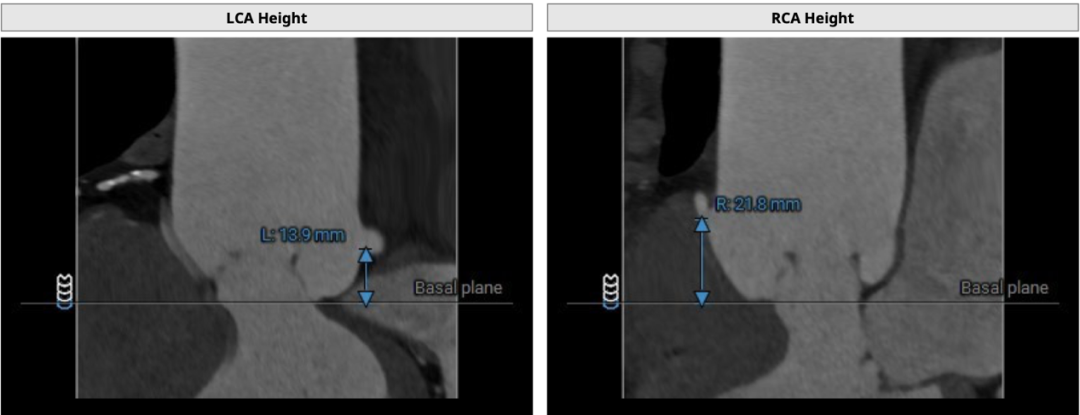

CT分析

双侧冠脉开口高度可LCA:13.9mm,RCA:21.8mm:

横位心: